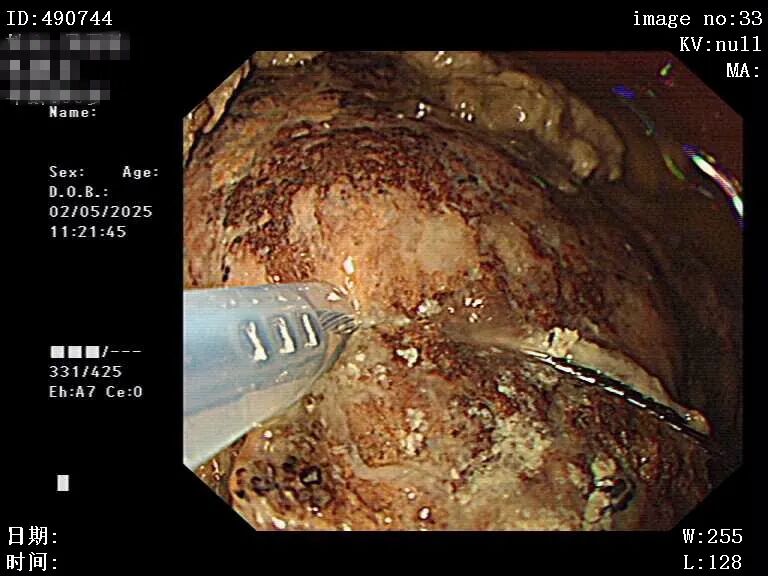

图片

碎石治疗